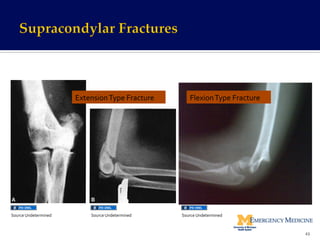

¡  Supracondylar Extension Fractures !

§  Most Common Type!

§  Mechanism of injury !

▪  Fall on outstretched arm with elbow in extension!

§  Imaging !

▪  Distal humerus fractures and humeral fragment displaced posteriorly!

▪  Sharp fracture fragments displaced anteriorly with potential for

injury of brachial artery and median nerve!

§  Treatment!

▪  Non-displaced fracture (Rare) = Immobilization in posterior splint!

▪  May be discharged home with close follow-up!

▪  Displaced fracture !

▪  Orthopedic Consultation and reduction!

▪  Patients with displaced fractures or significant soft tissue swelling require

admission for observation!

41

¡  Supracondylar Flexion Fractures (rare)!

▪  Direct blow to posterior aspect of flexed elbow!

§  Fractures are frequently open!

§  Imaging = Distal humerus fracture displaced anteriorly!

▪  Non-displaced fractures!

▪  Splint immobilization and early orthopedic follow-up!

▪  Displaced fractures !

▪  Orthopedic consultation for reduction !

▪  Patients with displacement and soft tissue swelling require admission!

42

Extension

Type

Fracture

Flexion

43

Source

Undetermined